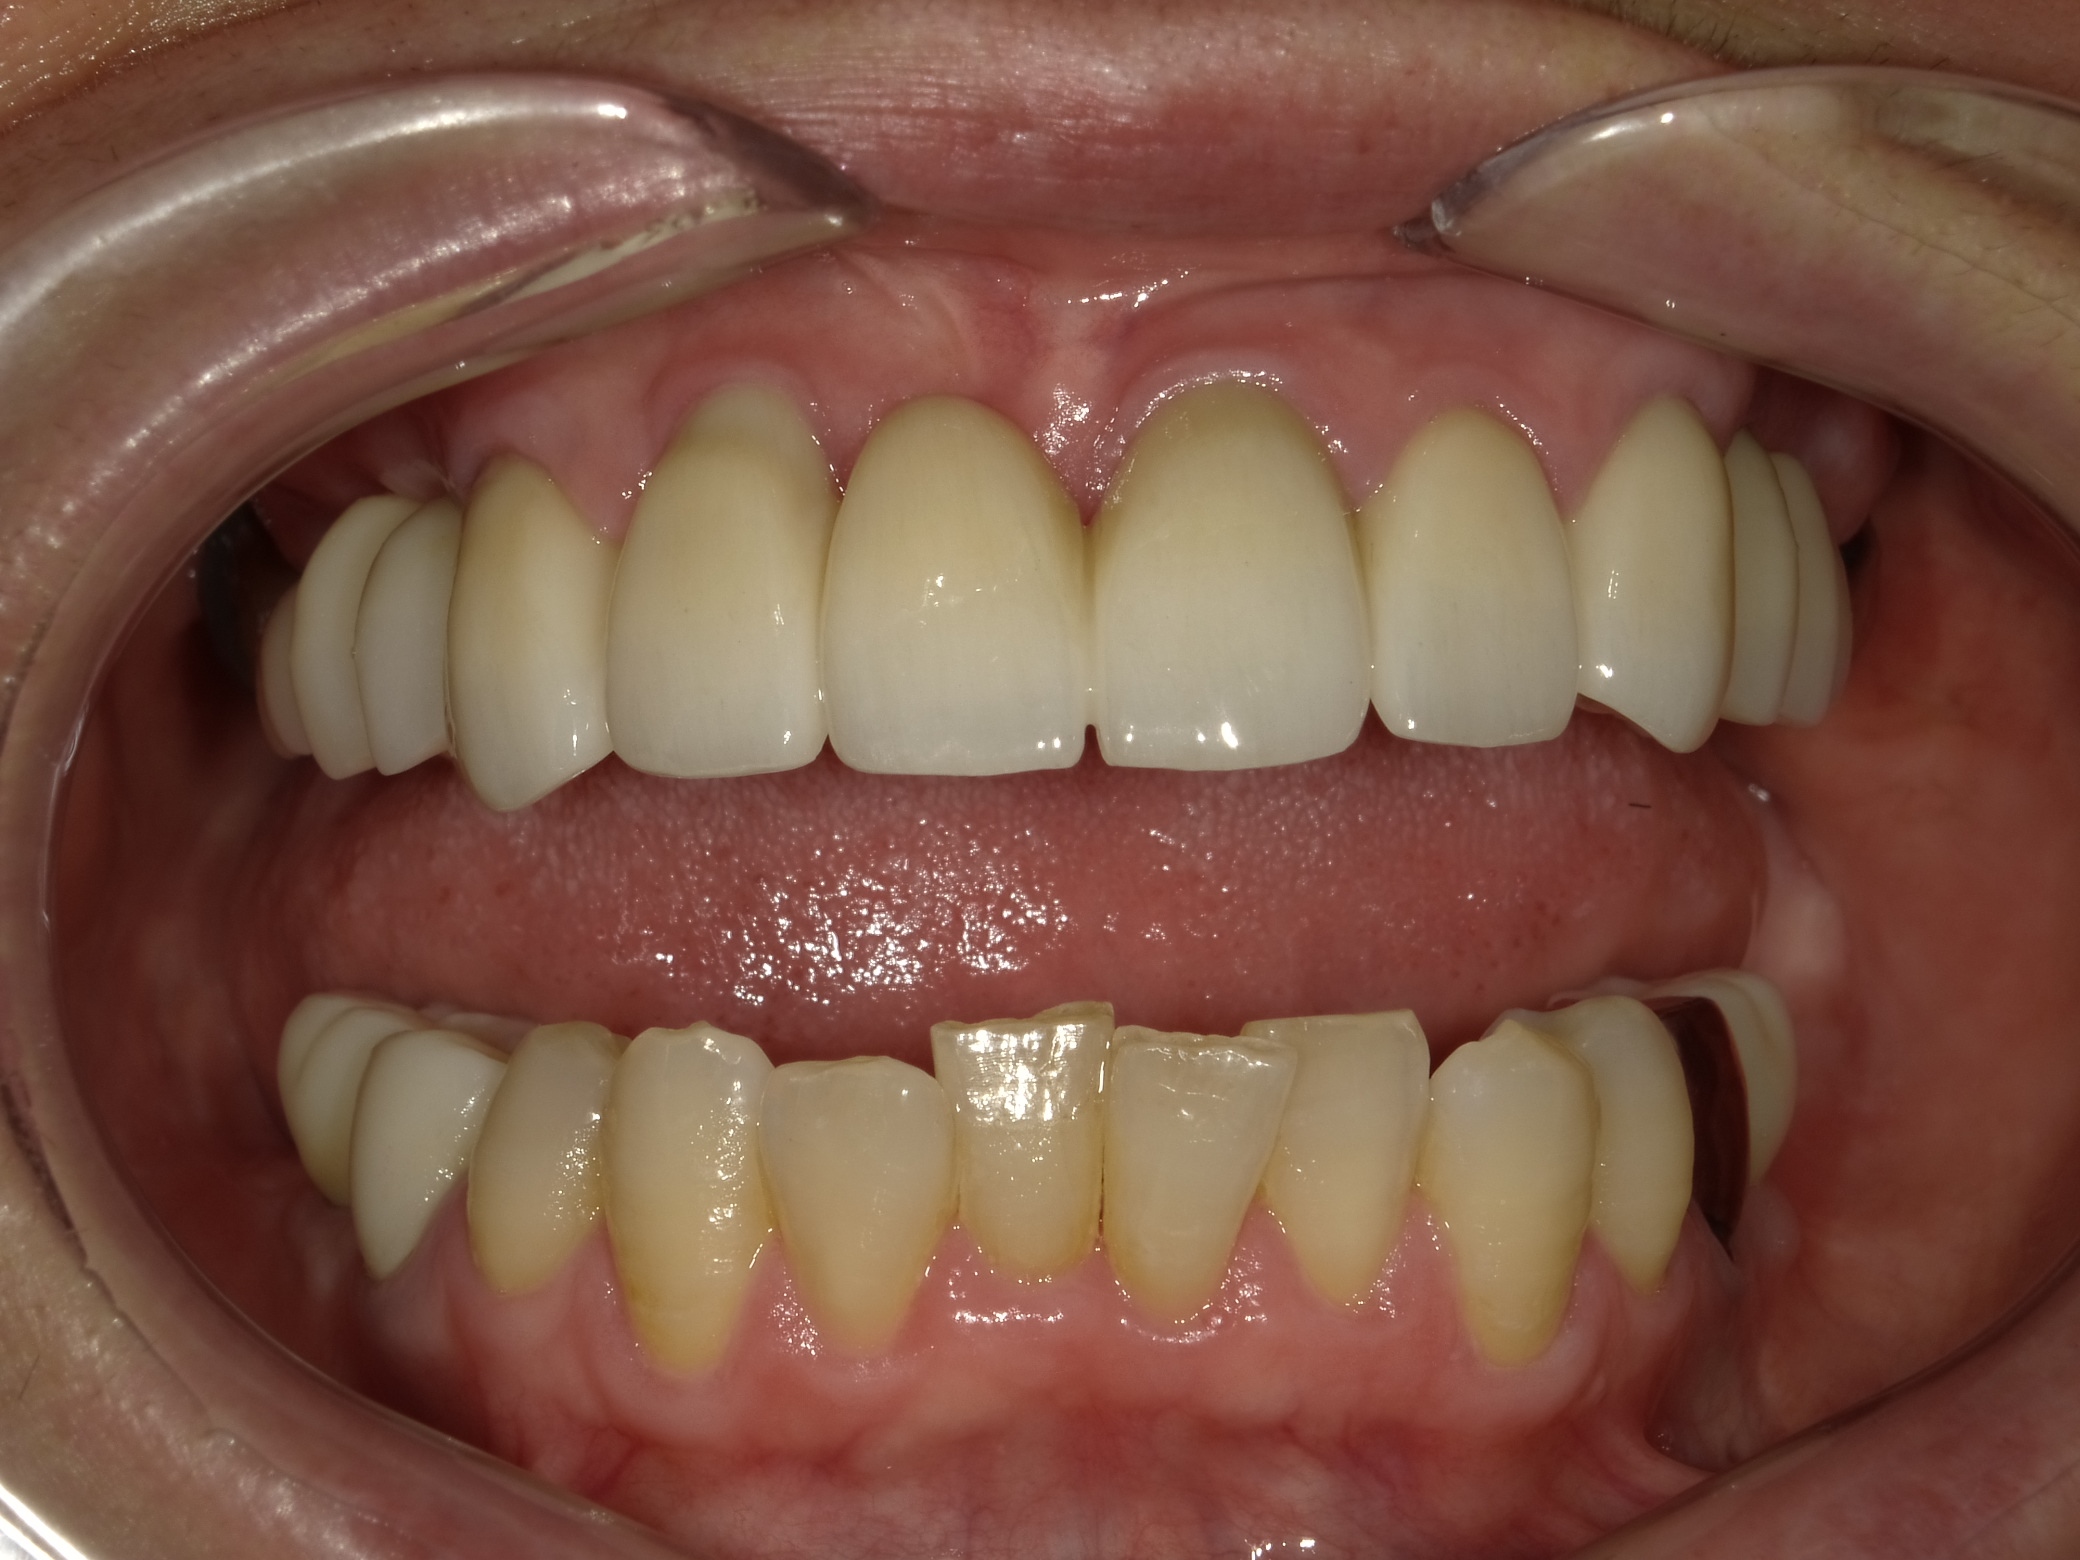

BEFORE

AFTER

主訴

全体的に見た目を綺麗にしたい。奥歯でしっかり噛みたい。

診断名・主な症状

臼歯部欠損

年齢

70歳

治療内容

インプラント埋入(右上4・6,左上4・6,右下6,左下6)

ジルコニアBr(右上3―左上3)

ジルコニア(右下5,左下5)

治療期間/

通院回数

インプラント 1年5ヶ月/13回

ジルコニアBr、ジルコニアクラウン 3ヶ月/10回

費用

インプラント: 2,552,000円

その他治療: 640,000円

合計 3,192,000円

*いずれも税込